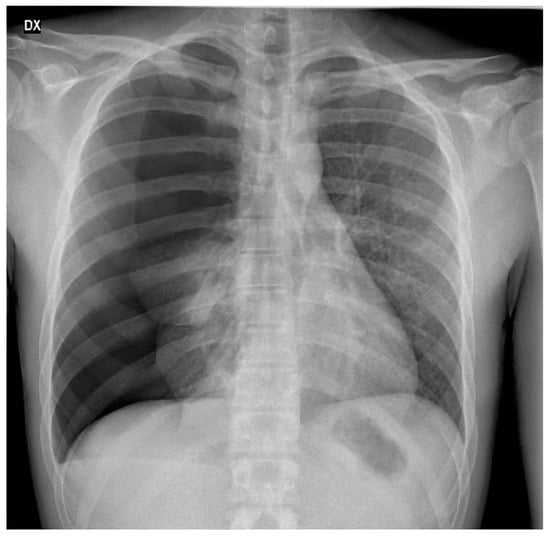

3.1. Case 1